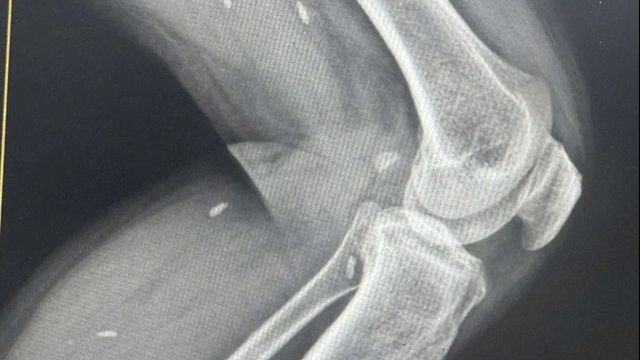

Qua thăm khám lâm sàng, các bác sĩ nghi ngờ trẻ bị hóc dị vật đường hô hấp, nhiều khả năng là đầu ngòi bút. Bệnh nhi được chỉ định chụp CT ngực, kết quả ghi nhận dị vật dạng hình ống, bề dày thành khoảng 1,8mm, chiều dài khoảng 18mm, nằm tại phế quản thùy dưới bên trái, gây cản trở thông khí.